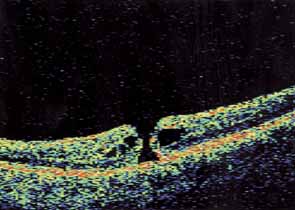

Optical coherence tomography or OCT is a relatively new tool used to diagnose macular lesions. It provides a unique view of the vitreoretinal architecture. OCT is particularly useful in diagnosing lamellar holes. With improvements in resolution and more widespread use, OCT will lead to new advances in the diagnosis and pathogenesis of macular holes (Fig. 2).